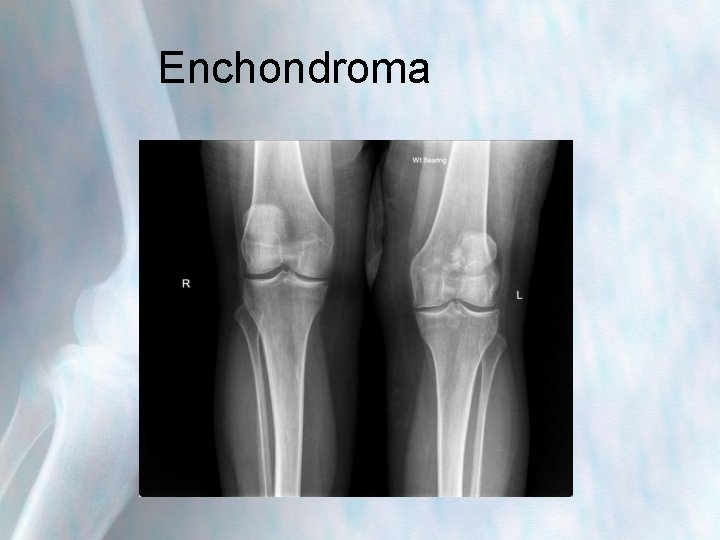

Enchondroma

Enchondroma • Benign bone tumour begins in the cartilage found inside the bones • Rarely cause symptoms often undiagnosed until xray taken for other reason • Majority do not require treatment, however can weaken bone if multiple tumours • Most common in patients btn 10 -20 years, and in small bones of hand; also femur, tibia and humorous • Can be difficult to distinguish from low grade chondrosarcomas and can transform to this-be suspicious if painful